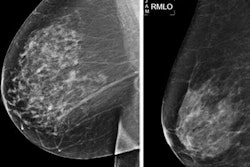

The study authors tested their method on 1,631 mediolateral oblique mammographic views collected from an open database. They found that the DCNN model achieved the best positioning classification accuracy of 78% using VGG-16 in the inframammary fold and classification accuracy of 73% using Xception in the nipple profile.